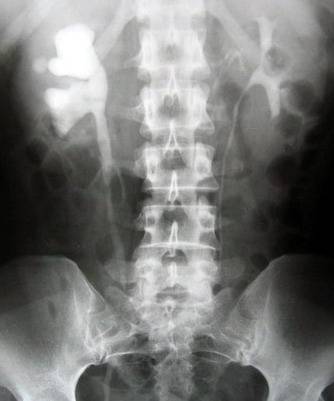

2、拍腹部平片:这是诊治尿路结石最有价值的检查,大约有95%的结石患者能在X线片上显影。必要时进一步做静脉肾盂造影,以了解肾功能和肾积水情况;

(三)X线检查:X线检查是诊断肾及输尿管结石的重要方法,约95%以上的尿路结石可在X线平片上显影。辅以排泄性或逆行性肾盂

输尿管造影 ,可确定结石的部位、有无梗阻及梗阻程度、对侧肾功能是否良好、区别来自尿路以外的钙化阴影、排除上尿路的其

它病变、确定治疗方案以及治疗后结石部位、大小及数目的对比等都有重要价值。密度低或透光怀石,加以输尿管、肾盂充气造影,

结石则显示更为清晰。